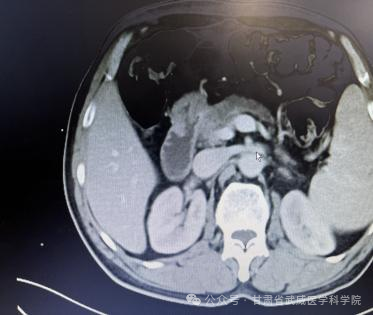

经过5周期化疗后复查腹部CT资料

胰腺癌一经确诊没有手术根治机会平均生存期在三个月到半年左右,部分患者能够手术根治切除,术后总体五年生存率不超过5%。本病发病率男性高于女性,男女之比为1.5~2:1,男性患者远较绝经前的妇女多见,绝经后妇女的发病率与男性相仿。胰腺癌诊治困难主要在于其起病隐匿、转移迅速。武威肿瘤医院腹部外科凭借强大的技术力量,近日连续治疗了肝门胆管癌,胰腺癌等数例高难度患者,手术均成功实施,且患者均恢复顺利出院,我科2023年02月收治一例胰头部占位,经科主任仔细阅片、全科讨论后患者胰腺癌肿瘤侵犯门静脉(环周超过1800)及胃十二指肠动脉无外科切除机会,经过术前五周期全身静脉化疗(吉西他滨1000㎎/m2+白蛋白结合型紫杉醇125㎎/m2 D1、8)后CT评估该患者胰腺癌瘤体明显缩小,肿瘤与门静脉主干、胃十二指肠动脉之间有了一定的间隙,与患者家属积极交代病情及沟通后于2023-7-为该患者施行“根治性胰十二指肠切除+I125粒子植入术”,现恢复良好,总生存时间已超过1年。